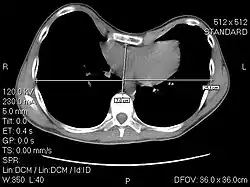

The Haller index, created in 1987 by J. Alex Haller, S. S. Kramer, and S. A. Lietman,[1] is a mathematical relationship that exists in a human chest section observed with a CT scan. It is defined as the ratio of the transverse diameter (the horizontal distance of the inside of the ribcage) and the anteroposterior diameter (the shortest distance between the vertebrae and sternum).[2]

- distance 1 is the distance of the inside ribcage (at the level of maximum deformity or at the lower third of the sternum)

- distance 2 is the distance between the sternal notch and vertebrae.

A normal Haller index should be about 2.5. Chest wall deformities such as pectus excavatum can cause the sternum to invert, thus increasing the index.[6][7] In severe asymmetric cases, where the sternum dips below the level of the vertebra, the index can be a negative value.[8]